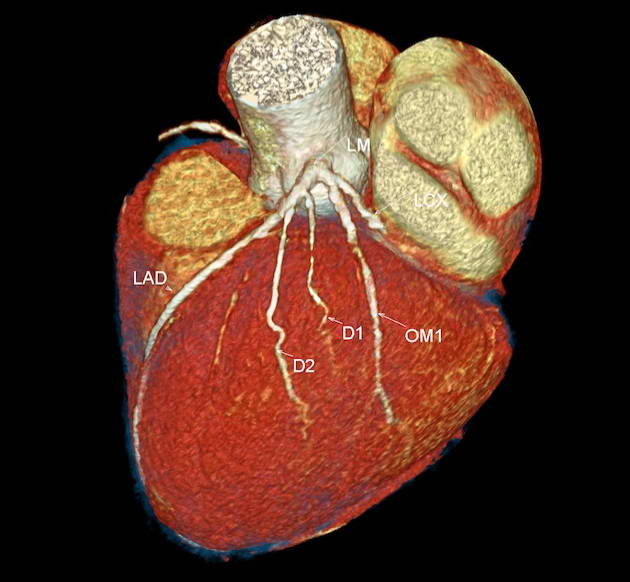

Cardiac CT

CARDIAC CT. Explained.